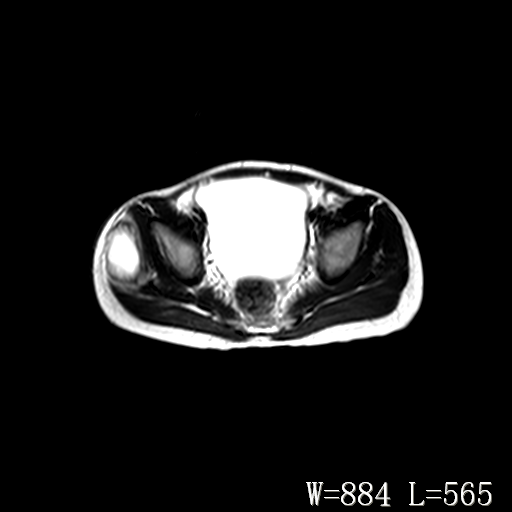

男,6岁,发现右臀部肿块10余天。

右侧臀部较大囊性肿块,长t1、长t2信号改变,周围组织信号正常,不知有否局部注射史?如果有,则支持脓肿,否则要考虑血管瘤可能。